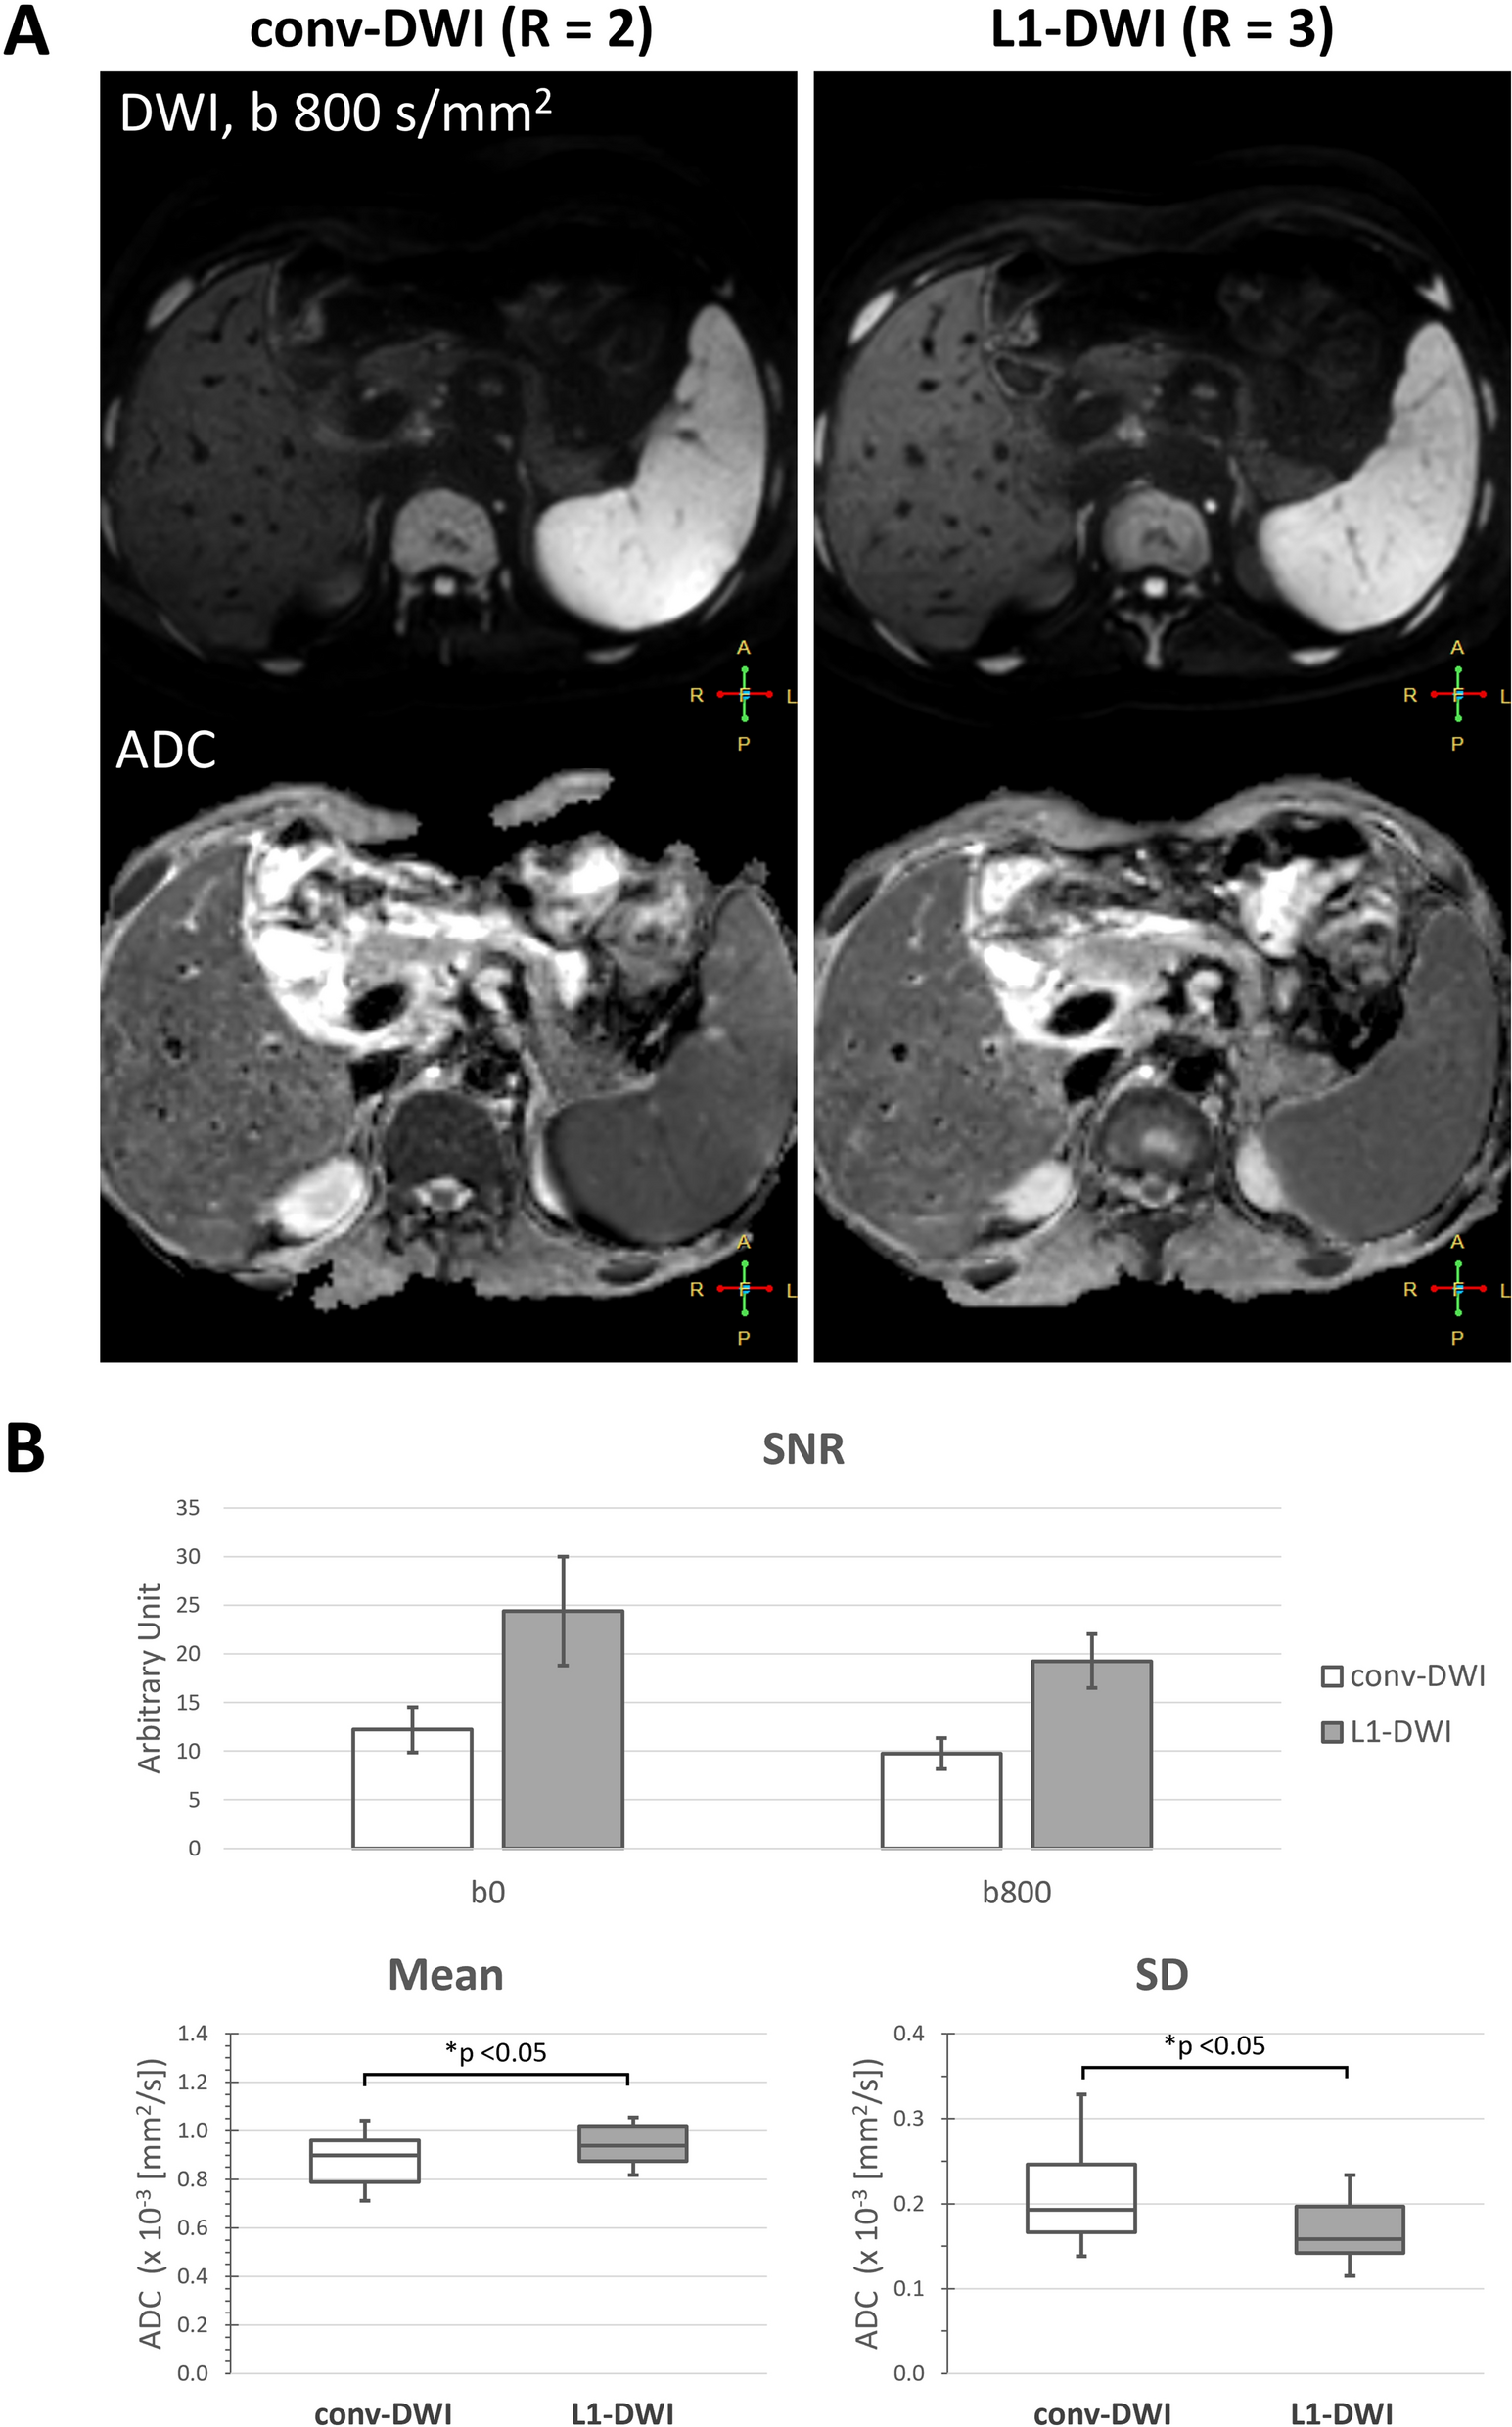

Figure 2

Comparison between liver conv-DWI (left) and L1-DWI (right) in healthy volunteers. conv-DWI = single-shot EPI-based DWI with parallel imaging reconstruction. L1-DWI = single-shot EPI-based DWI with L1-regularized iterative reconstruction. SD = standard deviation. (A) Images of a 35-year old volunteer of DWI at b = 800 s/mm2, and the resulting ADC image. (B) Higher SNR in DWI for both b = 0 and 800 s/mm2, as well as less variable ADC values were observed in L1-DWI in comparison to conv-DWI in 12 volunteers.